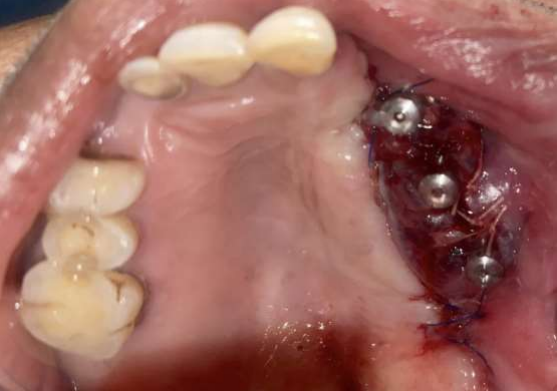

The PSI was designed to gain anchorage from the zygomatic and the nasomaxillary buttress with soft tissue coverage being accomplished using pedicled temporalis flap tunnelled below the zygomatic arch (Figure 6,7).

Figure 6: PSI fixation

Figure 6